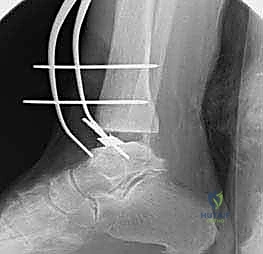

تعتمد دقة الجراحة على المحاذاة الصحيحة. يتم استخدام أجهزة توجيه متطورة (Jigs) تثبت على عظمة الساق باستخدام دبابيس معدنية. يتم التحقق من صحة الزوايا والمحاور باستخدام جهاز الأشعة السينية المباشر داخل غرفة العمليات (C-arm Fluoroscopy). يضمن الدكتور هطيف أن يكون القطع موازياً للأرض تماماً عند وقوف المريض.